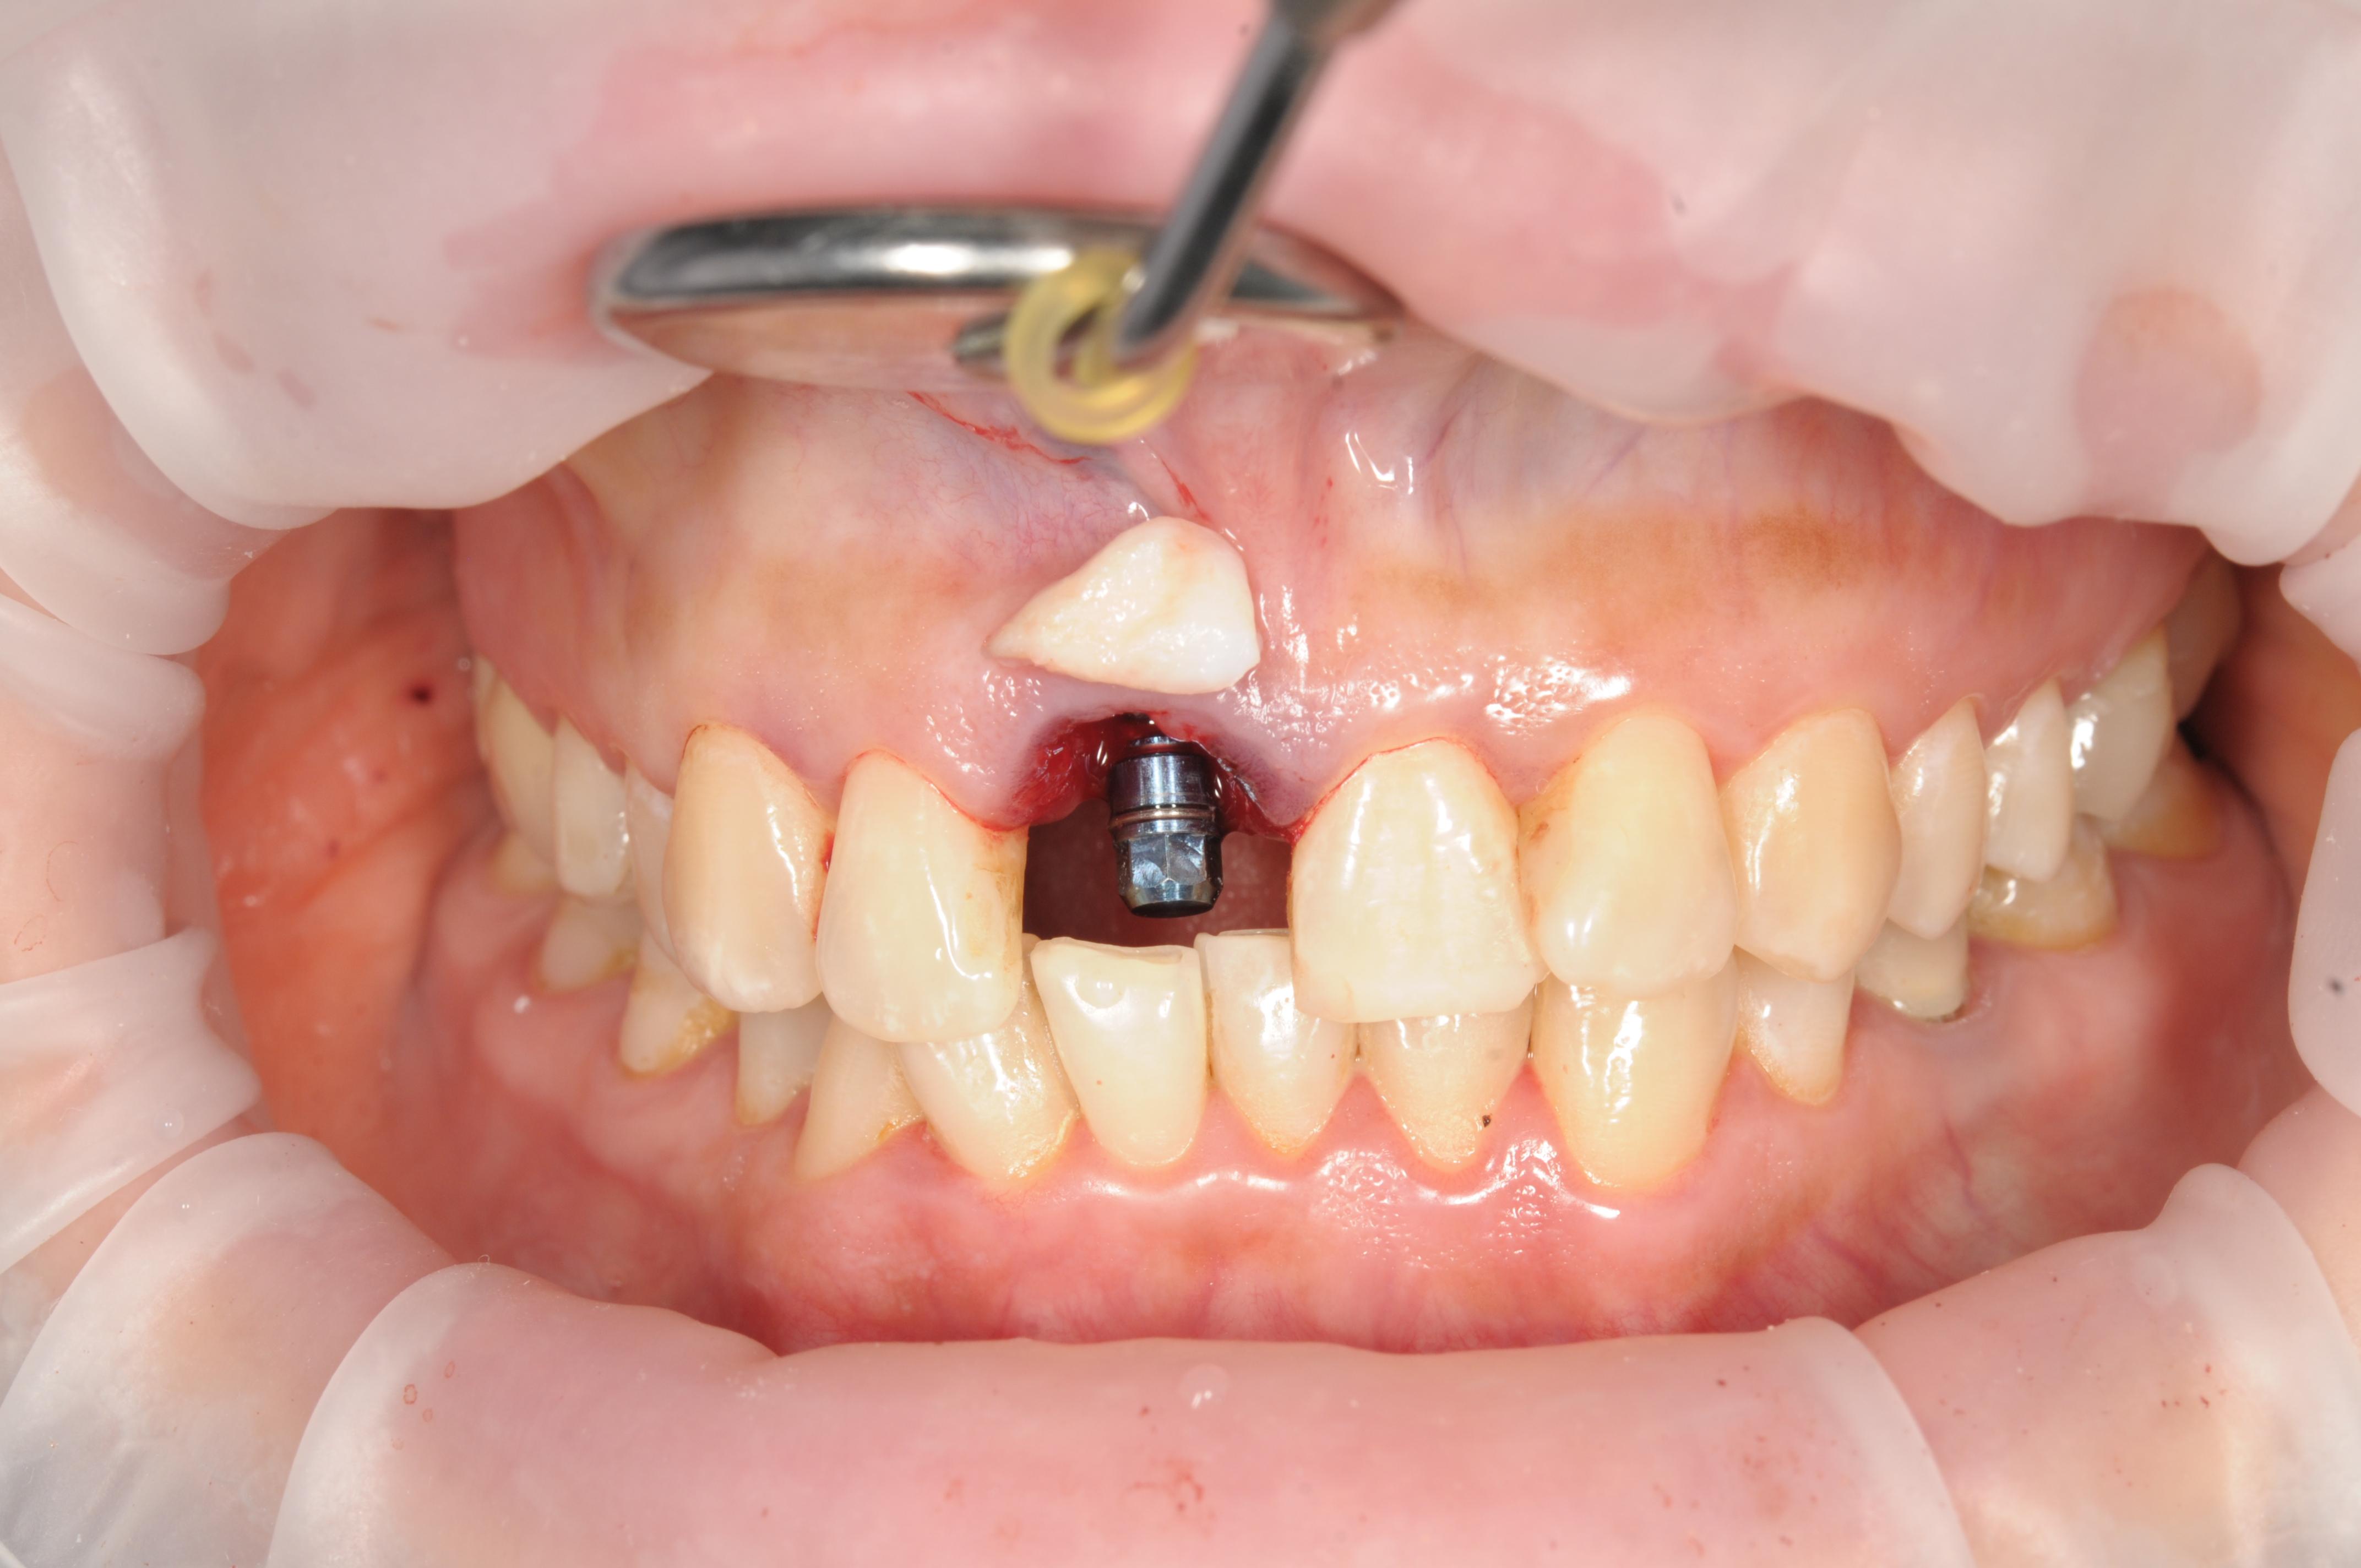

Имплантация

• Установка импланта Osstem

от 35 000₽